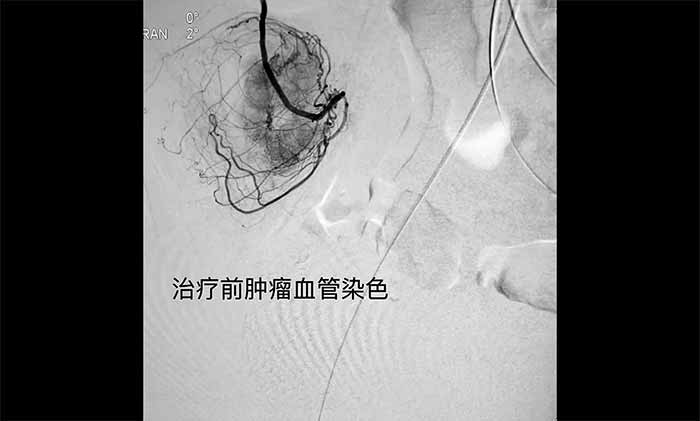

▲ 手術(shù)前腫瘤血管染色

術(shù)中,王永利教授聯(lián)合侯安繼主任、黃運(yùn)星醫(yī)生,首先根據(jù)造影圖像,確認(rèn)導(dǎo)管在腫瘤供血?jiǎng)用}分支內(nèi)。經(jīng)微導(dǎo)管灌注化療藥物,并對(duì)血管進(jìn)行栓塞。完成后經(jīng)微導(dǎo)管造影,見(jiàn)腫瘤血管供血和染色已明顯減少。術(shù)后,便血已基本得到控制。